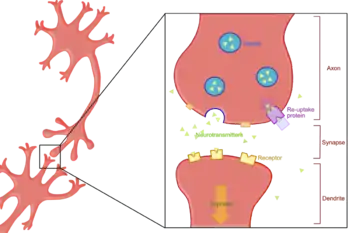

Reuptake is the reabsorption of a neurotransmitter by a neurotransmitter transporter located along the plasma membrane of an axon terminal (i.e., the pre-synaptic neuron at a synapse) or glial cell after it has performed its function of transmitting a neural impulse.

Reuptake is necessary for normal synaptic physiology because it allows for the recycling of neurotransmitters and regulates the level of neurotransmitter present in the synapse, thereby controlling how long a signal resulting from neurotransmitter release lasts. Because neurotransmitters are too large and hydrophilic to diffuse through the membrane, specific transport proteins are necessary for the reabsorption of neurotransmitters. Much research, both biochemical and structural, has been performed to obtain clues about the mechanism of reuptake.

The classic transporter proteins use transmembrane ion gradients and electrical potential to transport neurotransmitter across the membrane of the presynaptic neuron. Typical neurotransmitter sodium symport (NSS) transporters, which are Na+ and Cl− ion dependent, take advantage of both Na+ and Cl− gradients, inwardly directed across the membrane. The ions flow down their concentration gradients, in many cases leading to transmembrane charge movement that is enhanced by the membrane potential. These forces pull the neurotransmitter substrate into the cell, even against its own concentration gradient. At a molecular level, Na+ ions stabilize amino acid binding at the substrate site and also hold the transporter in an outward-open conformation that allows substrate binding.[4] The role of the Cl− ion in the symport mechanism has been proposed to be for stabilizing the charge of the symported Na+.[5][6]

The main objective of a reuptake inhibitor is to substantially decrease the rate by which neurotransmitters are reabsorbed into the presynaptic neuron, increasing the concentration of neurotransmitter in the synapse. This increases neurotransmitter binding to pre- and postsynaptic neurotransmitter receptors. Depending on the neuronal system in question, a reuptake inhibitor can have drastic effects on cognition and behavior. Non-competitive inhibition of the bacterial homologue LeuT by tricyclic antidepressants resulted from binding of these inhibitors in the extracellular permeation pathway.[9][10] However, the competitive nature of serotonin transport inhibition by antidepressants suggests that in neurotransmitter transporters, they bind in a site overlapping the substrate site.[11]